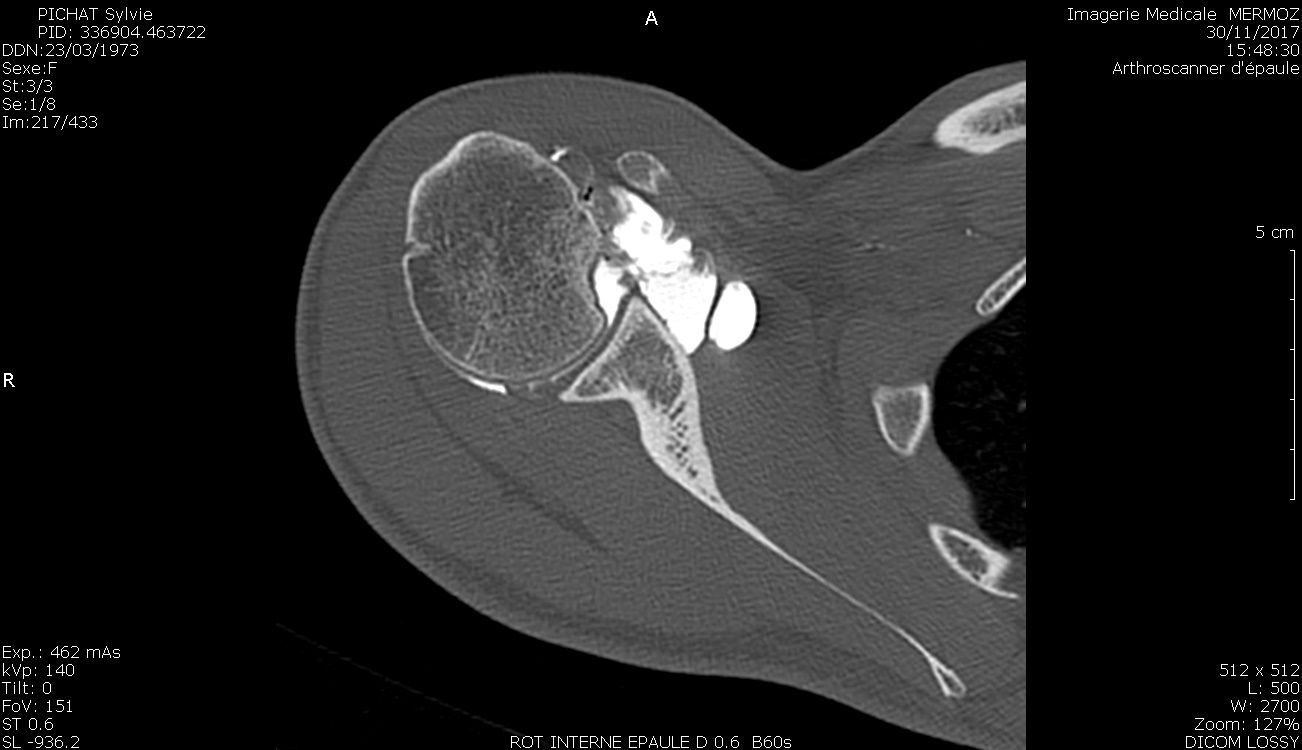

Mise au point Résultats et facteurs pronostiques des luxations postérieures de l’épaule , Arnaud Godenèche Centre orthopédique Santy, Hôpital Privé Jean Mermoz, Lyon, France , Steven Roulet Centre de l’épaule et de la main du Dauphiné-Groupe Elsan, Clinique Belledonne, St Martin d’Hères N°309 - Décembre 2021 ● 12 min de lecture